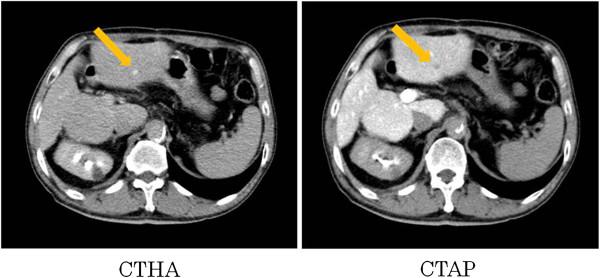

Inferior vena cava tumor thrombus that directly infiltrated from paracaval lymph node metastases in a patient with recurrent hepatocellular carcinoma.

Herein, we present the case of a patient with recurrent hepatocellular carcinoma (HCC) who had paracaval lymph node (LN) metastases with an inferior vena cava (IVC) tumor thrombus after a hepatectomy. A 65-year-old man with chronic hepatitis B virus infection received an extended anterior segmentectomy because of two hepatic tumors, located in segments 7 and 8. Histological examination of both resected specimens showed mostly moderately differentiated HCC with some poorly differentiated areas, and liver cirrhosis (A2/F4). Because the patient had an elevated α-fetoprotein serum level, abdominal computed tomography (CT) was performed. Abdominal CT revealed a 9-mm-diameter recurrent tumor in hepatic segment 3 and paracaval LN metastases with an IVC tumor thrombus at 8 months after the first operation. The patient received transcatheter arterial chemoembolization as treatment for the intrahepatic recurrence, following resection of the paracaval LN metastases and removal of the IVC tumor thrombus. In this case, the paracaval LN metastases had directly infiltrated the IVC via the lumbar veins, resulting in an IVC tumor thrombus, which usually develops from an intrahepatic tumor via the hepatic vein. The development of an IVC tumor thrombus with HCC recurrence, as in this case, is very rare, and based on a PubMed search, we believe this report may be the first to describe this condition.